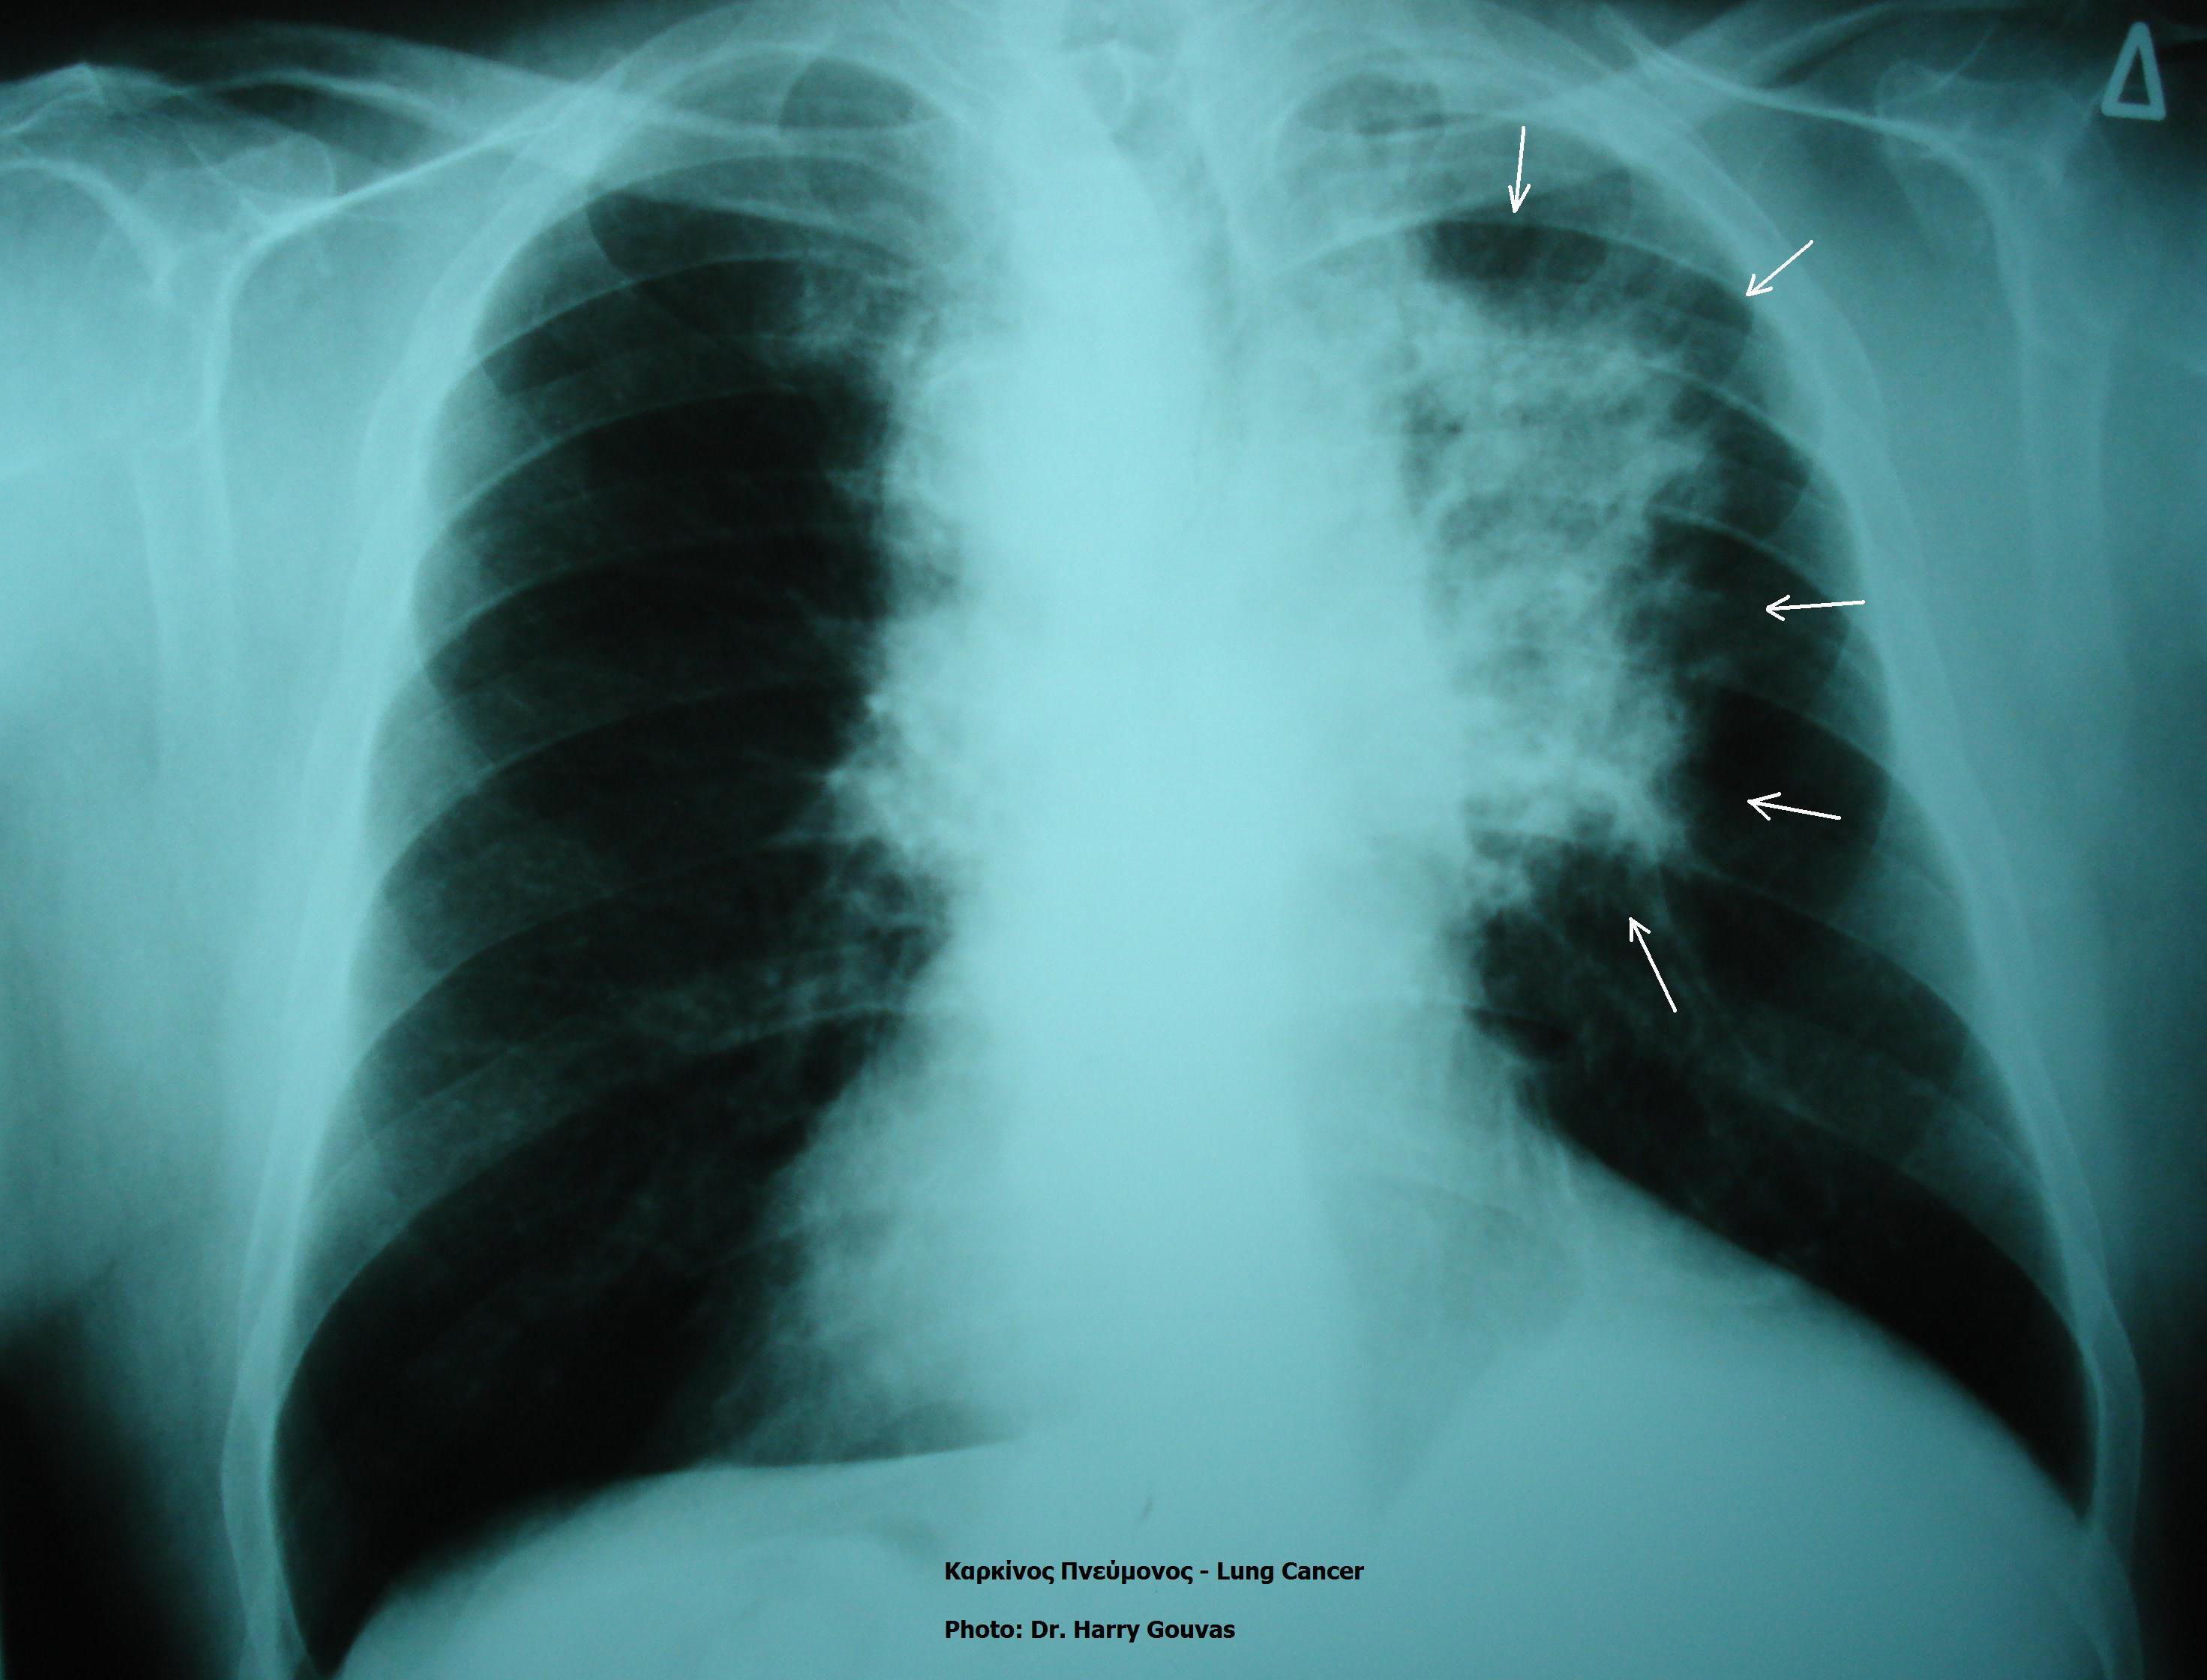

Онколог Нефедов: рак легких поражает курящих женщин

Статистика показывает, что риск развития рака легких у курящих женщин почти в два раза выше, чем у мужчин из-за низкой эффективности восстановления ДНК. На женский организм действие канцерогенов из сигарет более вредное.

Курение повышает вероятность развития интерстициальных заболеваний легких и обструктивной болезни легких. Со слов онколога, риск рака легких также увеличивается на фоне поражения интерстиций и туберкулеза.

Фото: Φωτογραφικό αρχείο Δρ. Χαράλαμπος Γκούβας, Δρ. Χαράλαμπος Γκούβας (Harrygouvas), Creative Commons Attribution-Share Alike 3.0 Unported license.